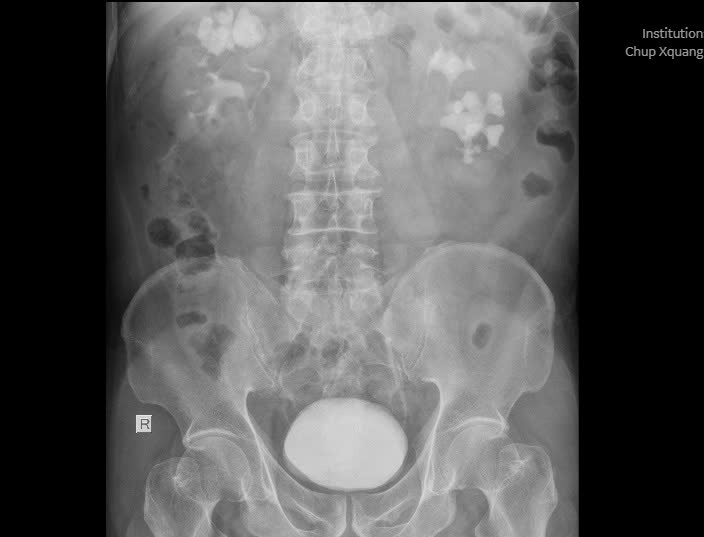

Kết quả thăm khám và xét nghiệm cho thấy bệnh nhân có sỏi ở cả hai bên thận, trong đó thận phải chứa một khối sỏi san hô kích thước lên đến 35x30x22mm, kèm nhiều viên nhỏ khác.

Hình ảnh X-Quang